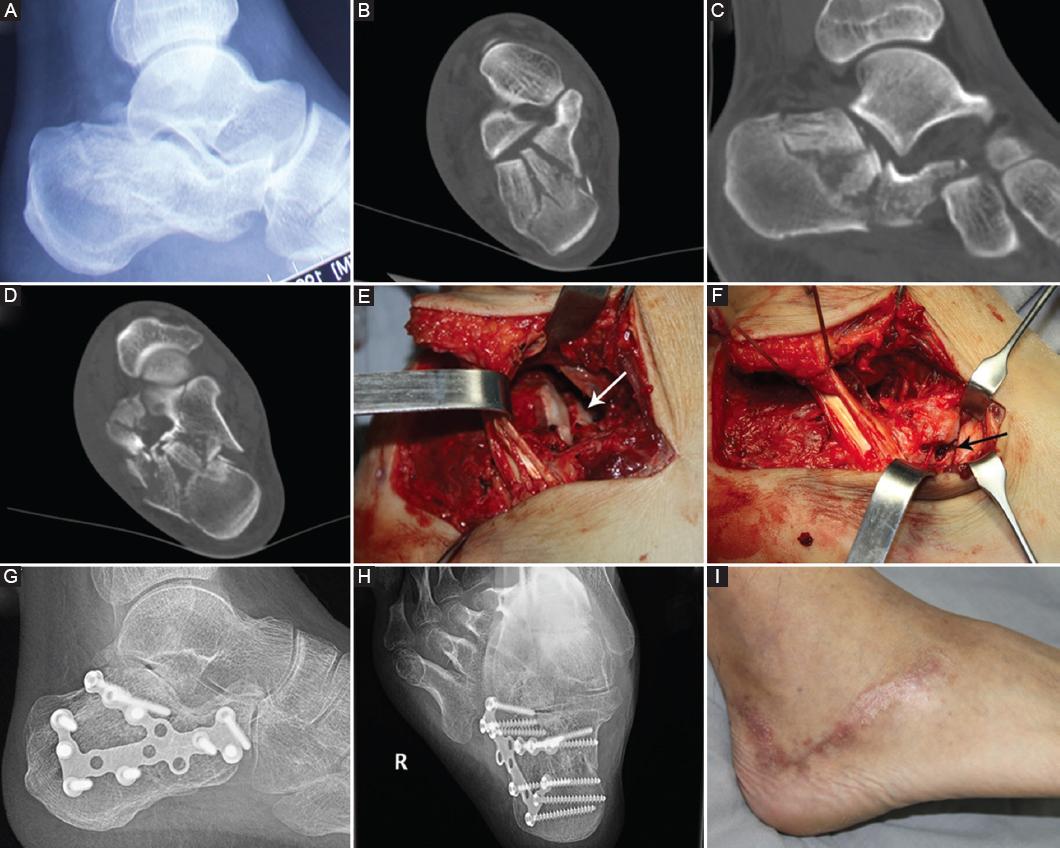

Figure 4 A: the lateral view of pre-operative radiographs. B-D: the images of the CT scan, Sanders type IIIBC. E: the fracture line of the posterior facet of calcaneus (white arrow). F: the fracture line involved the calcaneocuboid joint (black arrow). G and H: the lateral view and axial view of the post-operative radiographs. I: the healed lateral hook curvy incision.

The modified tarsal sinus incision adequately exposed the posterior facet, the lateral wall of the calcaneus, and the calcaneocuboid joint. A traction valgus of calcaneal tuberosity can correct varus deformity. With the talus articular surface as a reference, the inferior talus’ articular surface fracture block was restored through tarsal sinus poking and temporarily fixed with a K-wire (Fig. 4). The articular plane was reduced to squeeze the lateral wall of the calcaneus. Titanium bone plates of appropriate type were selected, trimmed, and shaped according to fracture morphology and then inserted into the lateral calcaneal bone after subperiosteal dissection. After the percutaneous insertion of the guide by the template positioning method, drilling holes and screws were inserted to fix the plate. All 25 cases were followed up for an average of 18.7 (12-24) months. Bone healing was achieved in all patients at 12-month follow-up. The skin incision healed well in all cases without necrosis, infection, or sural nerve damage (Fig. 4). The fracture had healed in all cases after an average period of 8 weeks (6-10 weeks). Due to the different elastic modulus and compositional structure of metal and bone, the stress shielding effect would occur, which could lead to the easy recurrence of fractures around the fixed object. Accordingly, the plate-screw internal fixers were removed in 12 patients through the original incision 1-3 years after surgery, and all of the incisions had healed well.